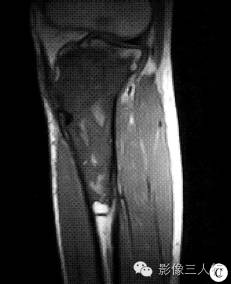

【病例】左胫骨弥漫性非霍奇金淋巴瘤1例X线MR影像表现

2.骨髓炎本例有近4个月的病程,加之无明显软组织肿胀及骨膜反应,考虑慢性低毒性骨感染。可以无急性感染史或感染症状不明显,实验室检查外周血白细胞不增高或增高不明显。影像表现局限性或缓慢性骨质破坏,少有死骨形成,多有病灶边缘骨质硬化,故可考虑本病。但本例骨质硬化较少,而病变范围较广,此点不是很符合。另一不符之处,在MRI影像上,病灶下界与正常髓腔分界较清晰。

PLB较特征的影像表现可概括为:①早期肿瘤仅在骨髓腔内生长,外形保持正常,此时在X线上可表现正常,或仅表现为病变骨质内斑点状的溶骨性低密度,随着肿瘤组织向骨内膜生长,浸润、侵入到骨皮质内,使病变骨呈膨胀性改变,骨皮质呈“筛孔”或“鼠咬”状溶骨性破坏,破坏区边缘不清楚。②肿瘤的MR信号强度与肿瘤内部的组织成分有关。瘤细胞密度高、纤维成分多时,其T1、T2信号强度都相对较低。③骨膜反应较轻微。偶见的骨膜反应为单层型、板层型和针刺状,这种类型的骨膜反应在其他类 型骨原发恶性肿瘤中很少见到。④PLB的增强后MRI常为较均匀的中等或明显强化。⑤PLB的软组织肿块多以病变骨质为中心性,呈包绕性生长。